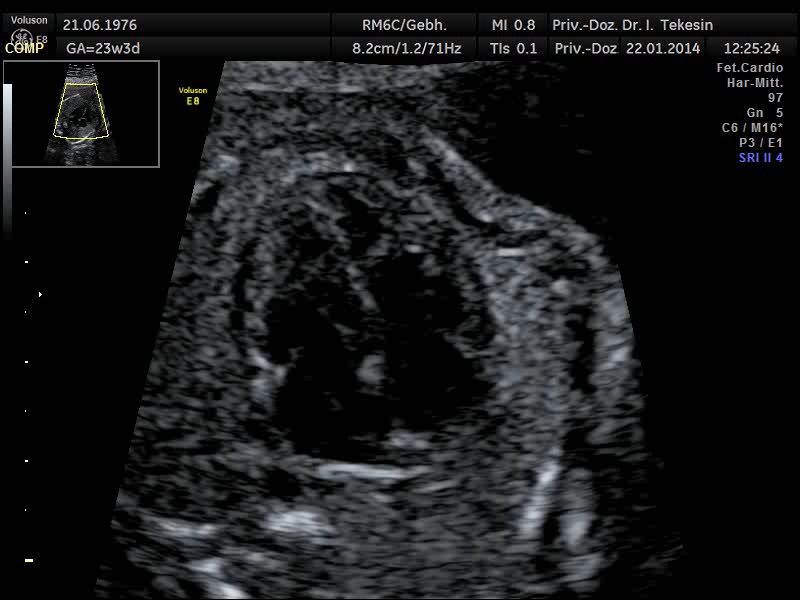

Normaler Vierkammer-­‐Blick

Normaler Vierkammer-Blick

Normales Herz in der 24. Woche

Normales Herz in der 22. Woche